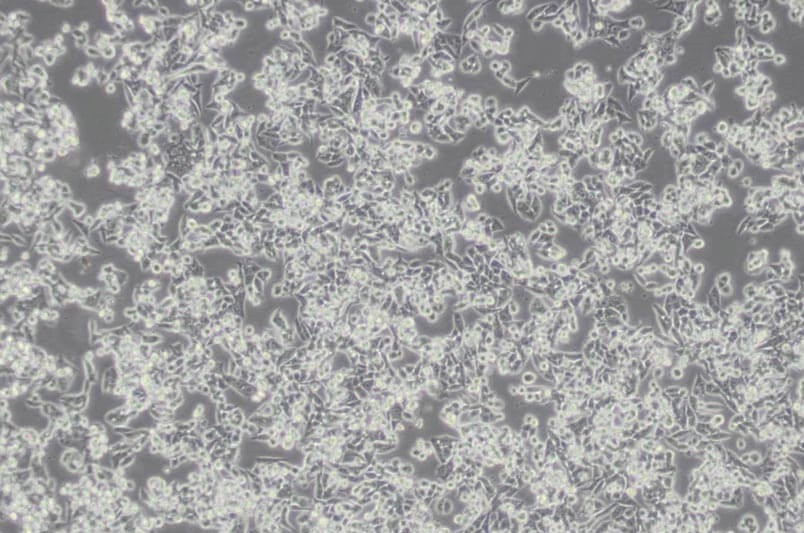

CW-2人結腸腺癌細胞

中文名稱 :人結腸腺癌細胞

細胞簡稱 :CW -2

細胞形態 :上皮細胞樣

生長特性 :貼壁細胞

CW -2細胞來源于結腸癌,C EA 陽性;C W -2細胞移植于裸鼠可成瘤。

組織來源 :結腸

細胞類型 :腫瘤細胞

腫瘤類型 :腸癌細胞